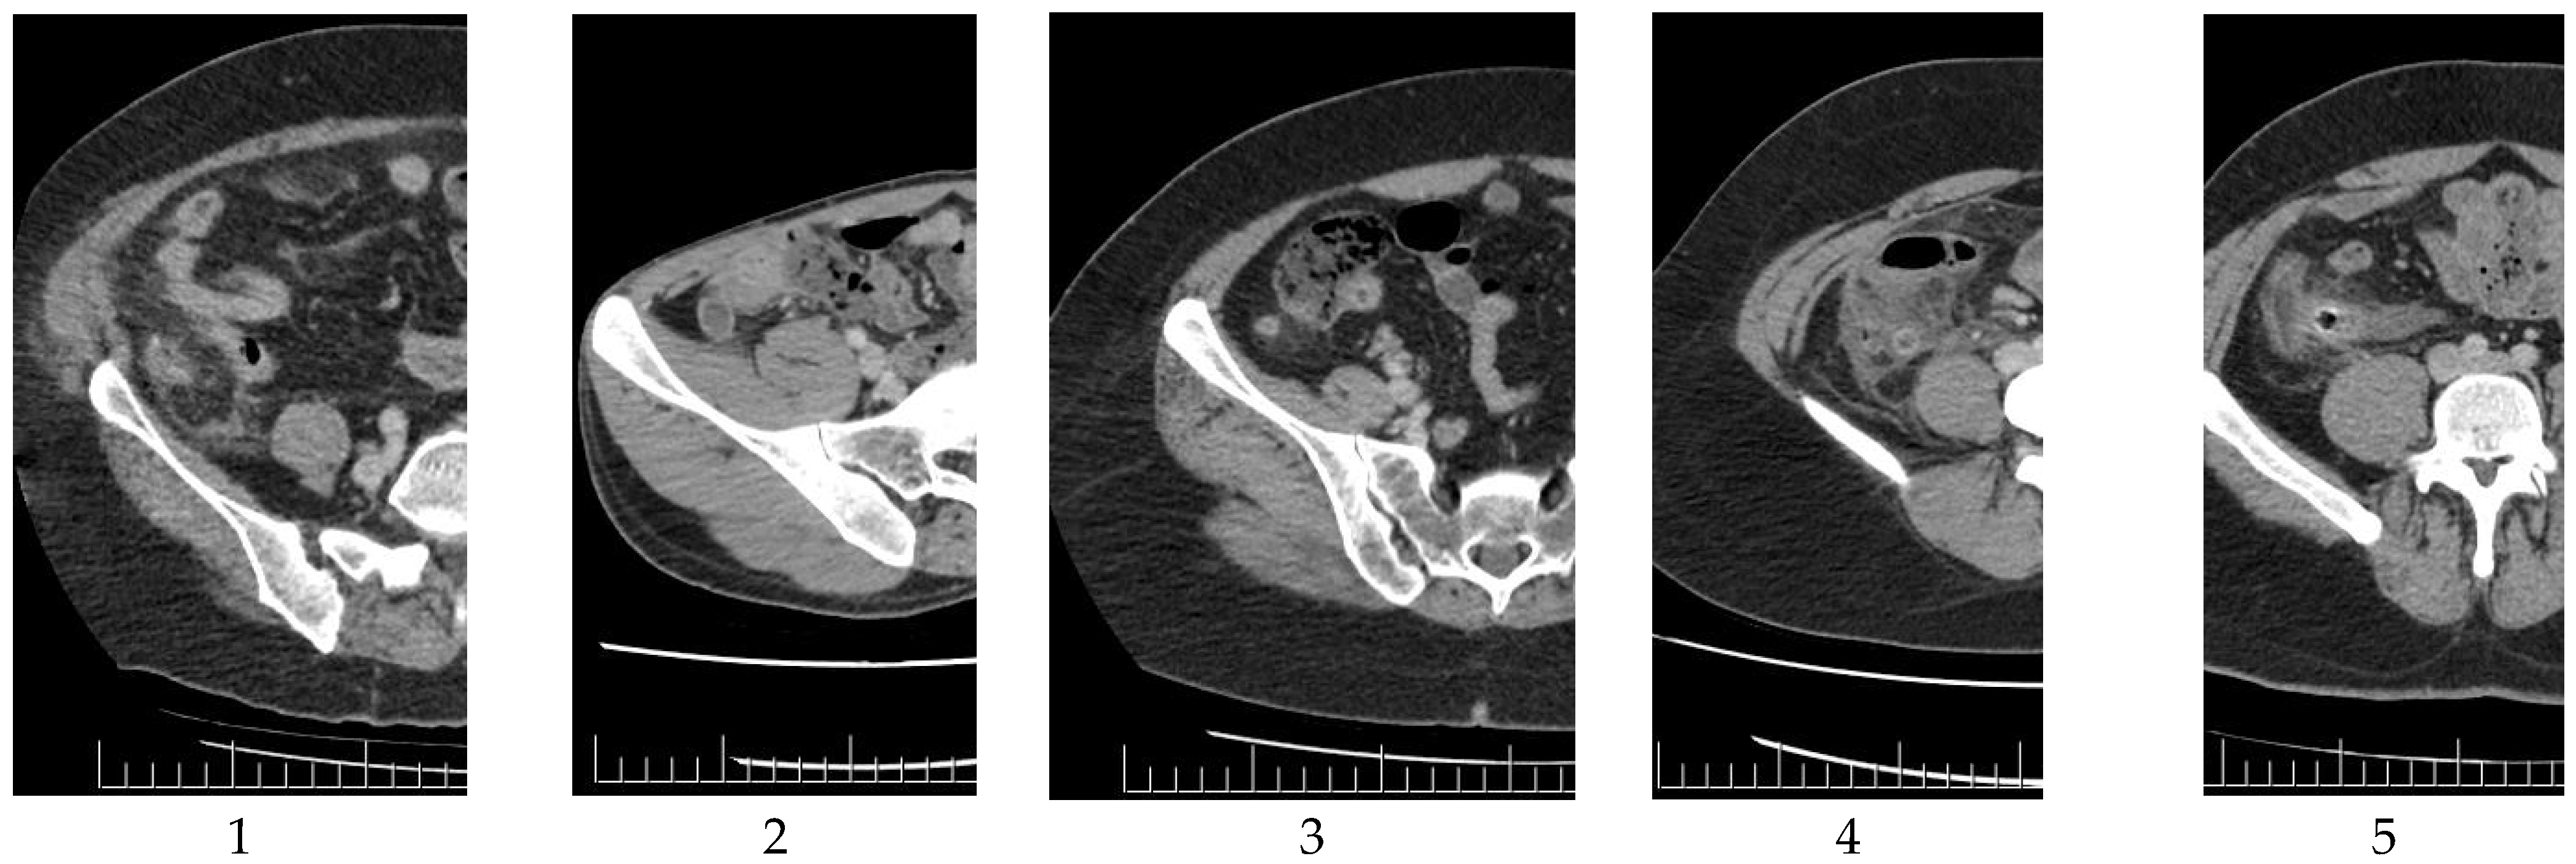

Group 1 included 66 patients, whereas Group 2 included 200 patients. The study criteria for Groups 1 and 2 are illustrated in Figure 1 and Figure 2, respectively.

4.2.2. Group 2

Group 2 consisted of cases that could be identified as AA by any radiologist based on CT. All patients in this group had CT findings that clearly indicated AA. The radiologists did not encounter any diagnostic challenges with this patient cohort.

Within this group, the following CT imaging criteria were established: appendiceal double-wall thickness ≥10 mm, wall thickness ≥6 mm, considerable peripheral inflammation, or the existence of appendicoliths.

Appendicoliths

This study focused only on the significance of the presence of appendicoliths and did not consider modifications in the diameter and lumen before and after nor the specific characteristics of the appendicolith, such as size, count, or position within the appendix. For all patients, identification was based on the presence of appendicoliths.

The success rate of AA diagnosis using deep learning was 96%. However, this rate should be increased to 100%. This rate can be enhanced by increasing the number of cases and/or studies conducted using various methodologies.

Figure 2. Study criteria for Group 2 (Left to right: 1. Significant edema with increased diameter; 2. Increased diameter without obvious edema; 3. Significant edema without a significant increase in diameter; 4. Slight increase in diameter with significant edema; and 5. Significant edema, increased diameter, and presence of fecaloid).